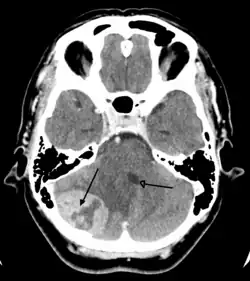

A posterior fossa tumor leading to mass effect and midline shift

There are no specific signs or symptoms for brain cancer, but the presence of a combination of symptoms and the lack of alternative causes may indicate a brain tumor.[41] A medical history aids in the diagnosis. Clinical and laboratory investigations will serve to exclude infections as the cause of the symptoms.

Brain tumors, when compared to tumors in other areas of the body, pose a challenge for diagnosis. Commonly, radioactive tracers are uptaken in large volumes in tumors due to the high activity of tumor cells, allowing for radioactive imaging of the tumor. However, most of the brain is separated from the blood by the blood–brain barrier (BBB), a membrane that exerts a strict control over what substances are allowed to pass into the brain. Therefore, many tracers that may reach tumors in other areas of the body easily would be unable to reach brain tumors until there was a disruption of the BBB by the tumor. Disruption of the BBB is well imaged via MRI or CT scan, and is therefore regarded as the main diagnostic indicator for malignant gliomas, meningiomas, and brain metastases.[41]